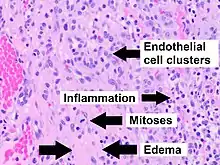

One study has suggested a correlation between pyogenic granulomas and Bartonella seropositivity.[8] However, this association has been questioned by others.[9] The microscopic appearance of a pyogenic granuloma consists of highly vascular granulation tissue. Inflammation is present. The lesion may have a fibrous character if it is older, and the surface may have ulcerations. Pyogenic granulomas rarely occur in the conjunctiva, cornea, or connective tissue of the eye following minor local trauma. Grossly, these mass lesions resemble those occurring at more common sites. The relationship of these lesions to lobular capillary hemangiomas of skin and oropharyngeal mucosa commonly referred to as pyogenic granuloma is uncertain.

Histopathological examination shows multiple capillaries (due to the vascular nature of the tumor), neutrophils (pyogenic), and necrotic tissue.